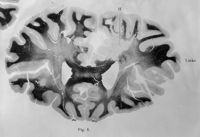

Image[Sans titre]